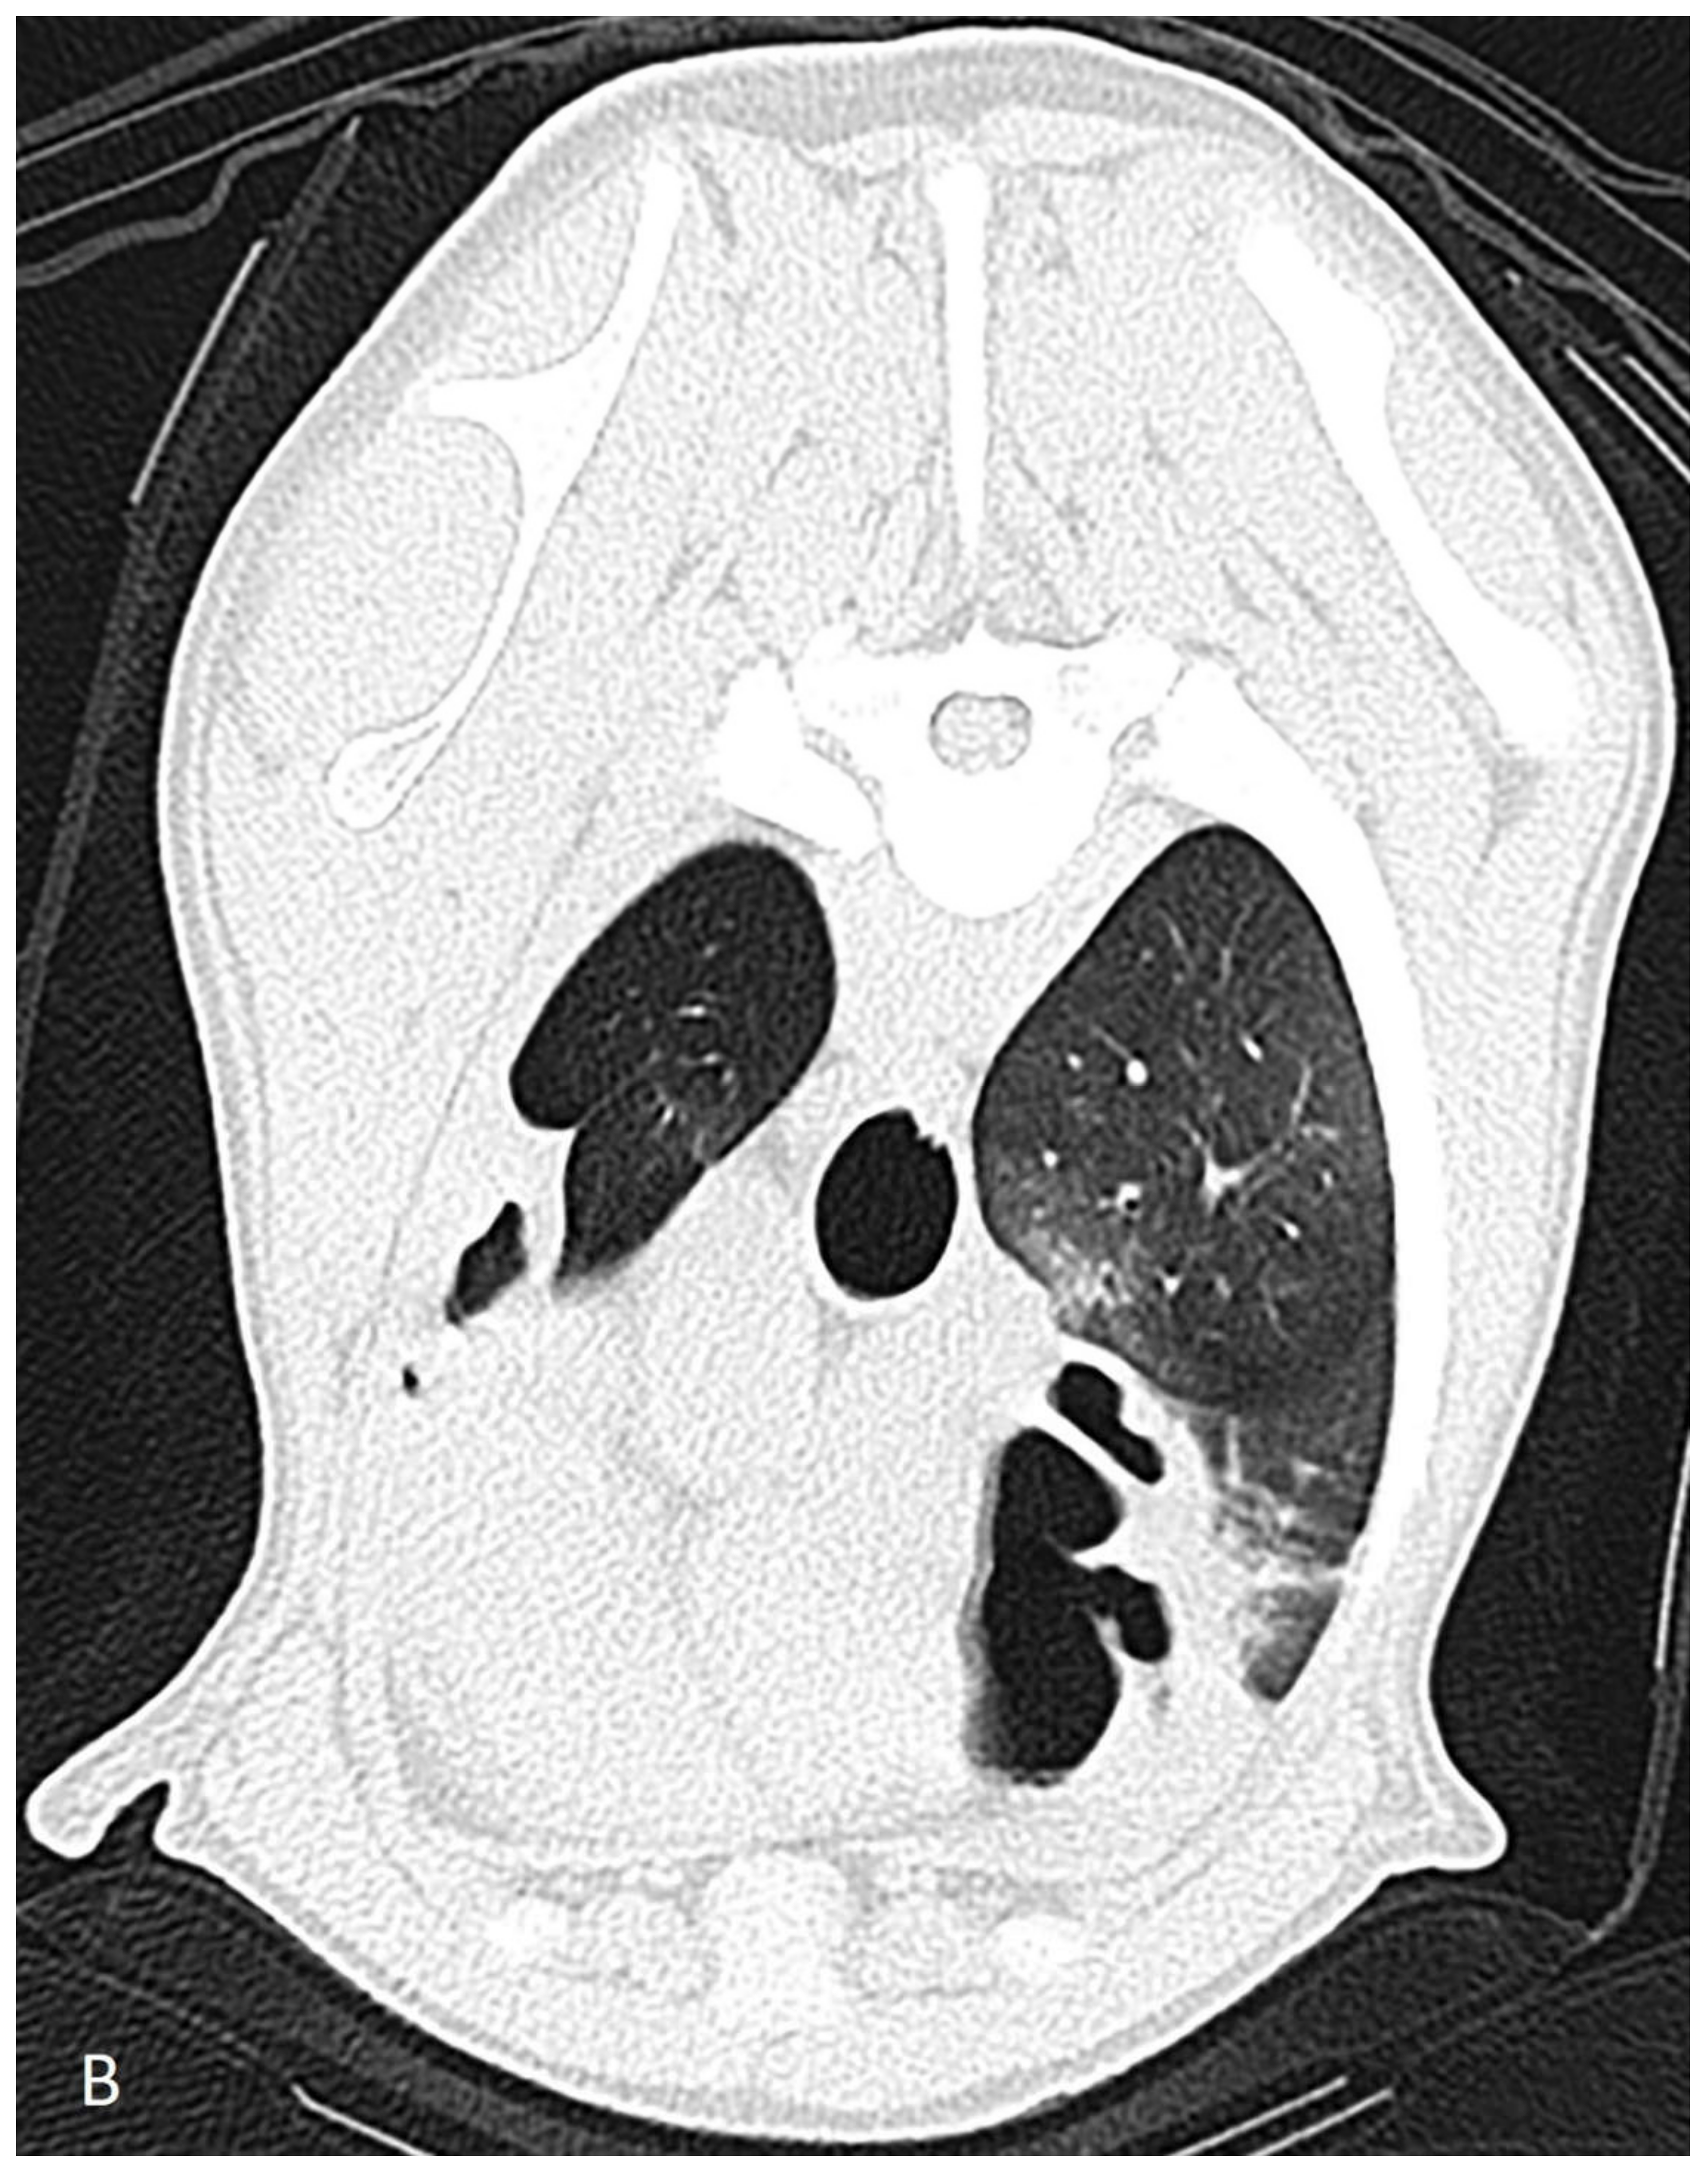

The dog was hospitalized and the next day a computed tomography scan, followed by a bronchoscopy and a bronchoalveolar lavage, were performed under general anesthesia. Computed tomography revealed severe dilation of the lobal bronchi of the left cranial, left caudal, right cranial, right middle and right accessory lung lobes (Figure 1). The rest of the bronchi showed thickened bronchial walls. The right sided lung lobes had a larger volume compared to those of the left, but the accessory lung lobe and the left cranial lung lobes were not aerated. Several poorly circumscribed interstitial to alveolar regions were noticed in the whole lung field in the peribronchial regions, most prominently in the right cranial lung lobe. The radiographically noticed soft tissue nodule was not recognized.

Figure 1. Computed tomographic scan of a 9-month-old German shepherd dog with multifocal bronchiectasis of unknown origin. Left of the animal is on the left side of the image. (A) Severe dilation of the lobal bronchus in the center of the left caudal lung lobe can be appreciated. The right caudal lung lobe has a larger volume compared to that of the left one and has normal tapering bronchi to the periphery. (B) Severe saccular dilation and lack of tapering to the periphery of the lobal bronchus of the right cranial lung lobe can be appreciated.